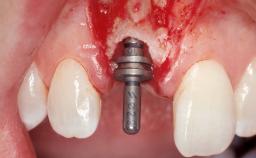

Immediate Flapless Placement of an Implant in a Maxillary Right Lateral Incisor Site

This 43-year-old male patient, a non-smoker, came to our practice because of a fracture of tooth 12 caused by a bicycle accident. Due to the combined para- and infrabony crown and root fracture, tooth extraction, and subsequent implant placement were suggested to the patient as the therapy of choice. The patient had high esthetic expectations with regard to the treatment outcome and asked for an immediate fixed provisional restoration. His individual esthetic risk profile summed up to a medium esthetic risk.

Placement Protocol Immediate implant placement

Tooth Site Maxillary incisor or canine

Loading Protocol Immediate